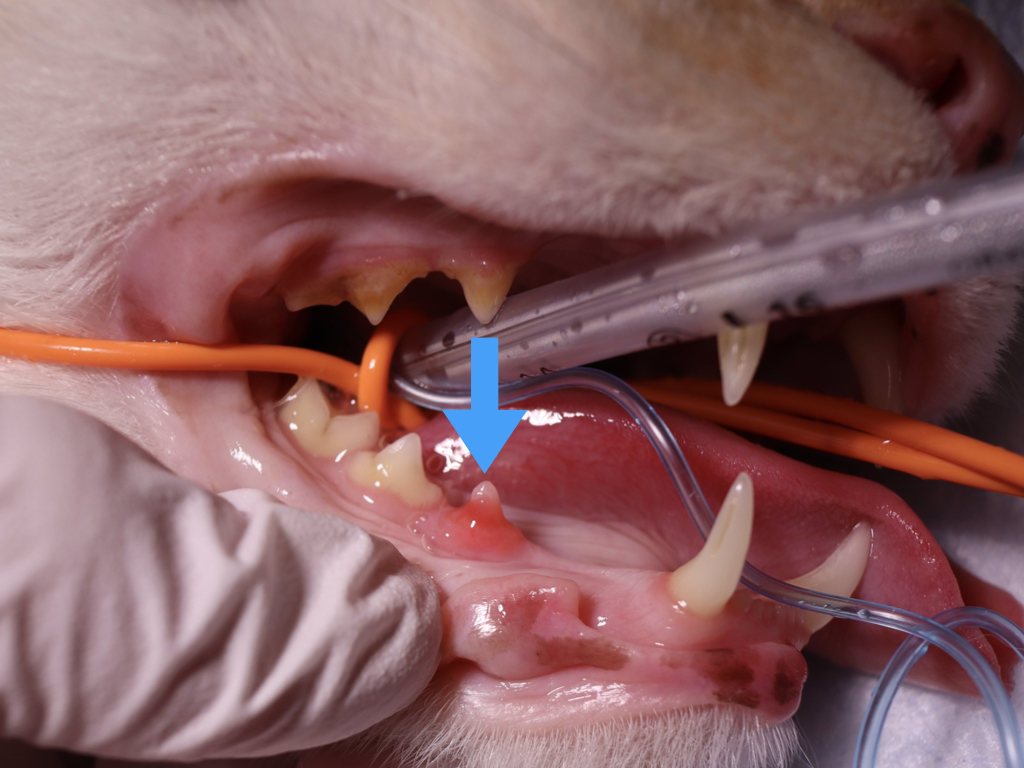

- 歯の表面がピンク色に見えるのは、内部からの吸収+肉芽組織の露出の可能性

- 歯ぐきに赤い肉のようなもの(肉芽組織)

吸収病巣は歯の内部で進行する病気のため、見た目だけでは正確な診断ができません。

歯科用レントゲンを撮影することで、病変の範囲や進行度、治療方針が明確になります。